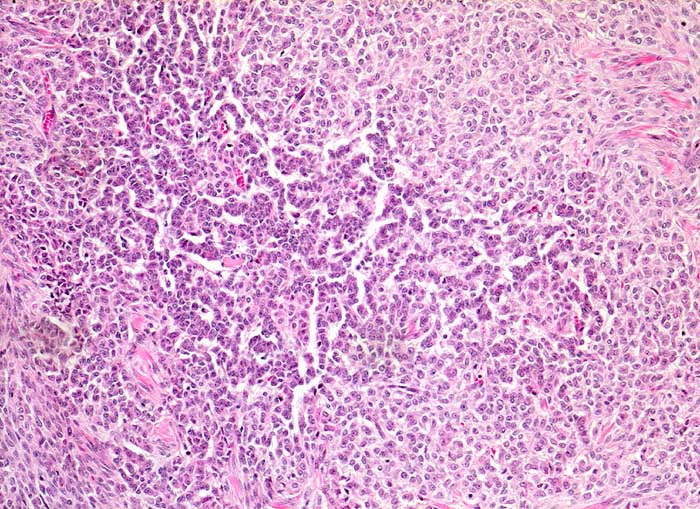

AP/ Granulosazelltumor des Ovars

Granulosazelltumor des Ovars

maligner Tumor

Ovar